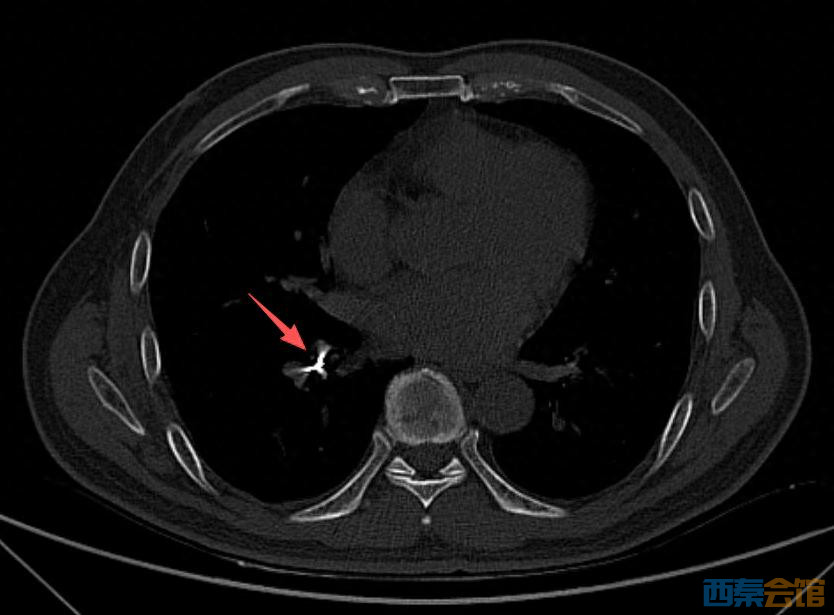

随后,诊所牙医陪同男子到北海市人民医院就诊,经 CT 检查,在患者右下肺支气管内发现有异物存留,便紧急收入呼吸与危重症医学科病房。

病房接诊后,医院立即启动急诊救治流程。医疗团队为患者取出异物,

经确认,取出的异物正是用于根管治疗的机扩针,长约 2 厘米,针的一头圆滑、一头细长而尖锐。

“幸好是圆滑的一头朝下滑进气管,一路滑到支气管没有造成意外损伤。”事后,医生表示。

术后检查确认,异物未对患者气道及肺部造成额外损伤,患者生命体征平稳。经过妥善观察治疗,患者次日康复出院。